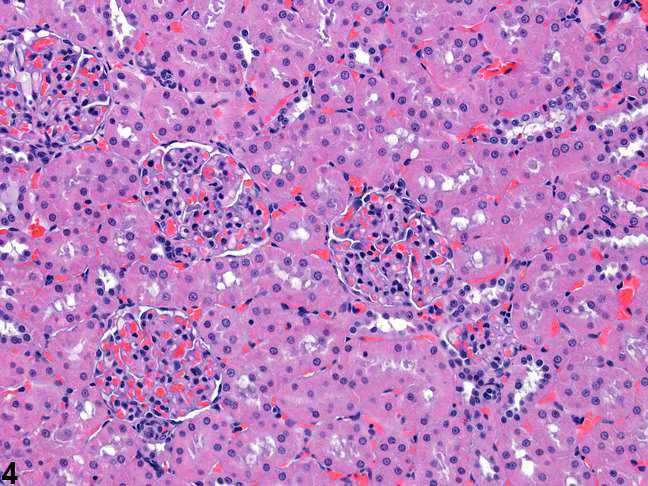

Kidney

Renal tubules and glomeruli

8. AlveoliKidney

1

2

3

41. Cortex,

2. Medulla,

3. Capsula,

4. Glomeruli

2. Bowman’s capsule